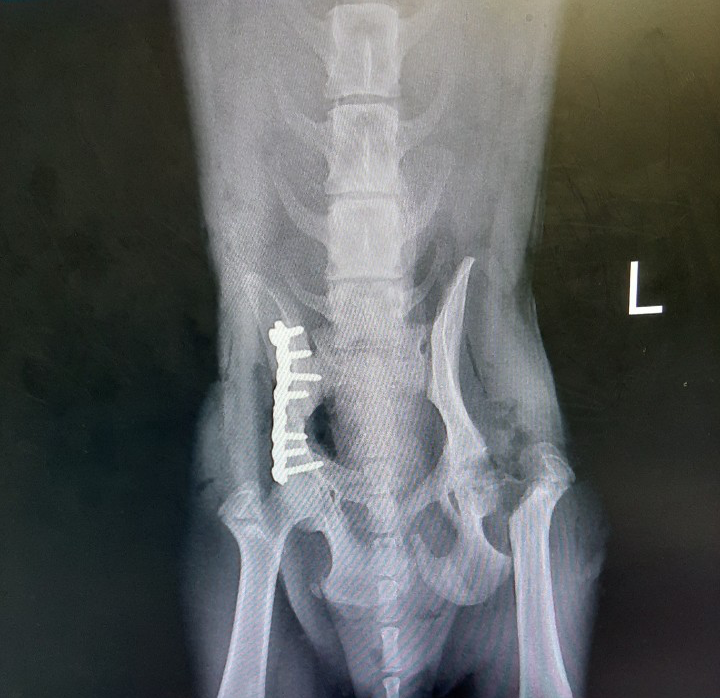

아이의 수술은 무사히 끝났지만, 입양처가 정해지지 않아 갈 곳이 없었다. 저 조그만 몸으로 철심을 박는 큰 수술을 견디고도 이 아이가 편히 쉴 작은 공간조차 없었다. 마침 나도 학기가 끝날 무렵이라 그간의 임시보호 경험을 바탕으로 임시보호에 자원했다.

(좌) 수술 직후의 아이 (우) 임시보호 시작